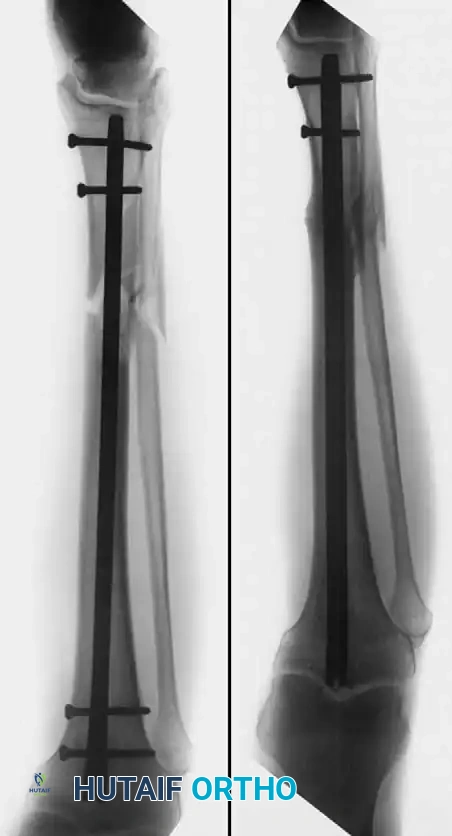

TIBIAL SHAFT NONUNIONS

Many treatment methods have been highly successful in obtaining union of tibial shaft nonunions. Union rates of 72.1% to 87.8% have been reported with closed bone grafting procedures in hypertrophic aseptic nonunions. Internal fixation (intramedullary nailing or plating) has been reported to obtain union in up to 98% of cases, and electrical stimulation in 78.8%.

The surgical technique selected depends heavily on whether the nonunion is hypervascular (hypertrophic) or avascular (atrophic), and whether the alignment of the fragments is satisfactory.

- Hypervascular Nonunions: The bone ends possess excellent biological capacity to unite but lack mechanical stability. In these cases, rigid internal fixation with a compression plate, an intramedullary nail, or a circular external fixator is usually all that is necessary. Supplemental bone grafting is rarely required.

- Avascular Nonunions: The bone ends are sclerotic, necrotic, and lack osteogenic potential. Rigid internal fixation must be supplemented by aggressive decortication of the sclerotic bone ends (shingling) and the application of autogenous bone graft. Weber and Brunner, Müller and Thomas, and Christensen have found these combined methods highly successful.

Judet and Patel reported excellent results treating 290 nonunions of the tibial shaft by internal fixation with plates and screws or intramedullary nails. The fragments were decorticated in all instances, but iliac cancellous grafts were rarely added. Clancey, Winquist, and Hansen treated 48 nonunions of the tibial shaft by Küntscher intramedullary nailing. In 30 cases, the nailing was completely closed, and in only 18 was open tibial osteotomy necessary to realign the fracture. Bone grafting was not used, and all but two nonunions healed.